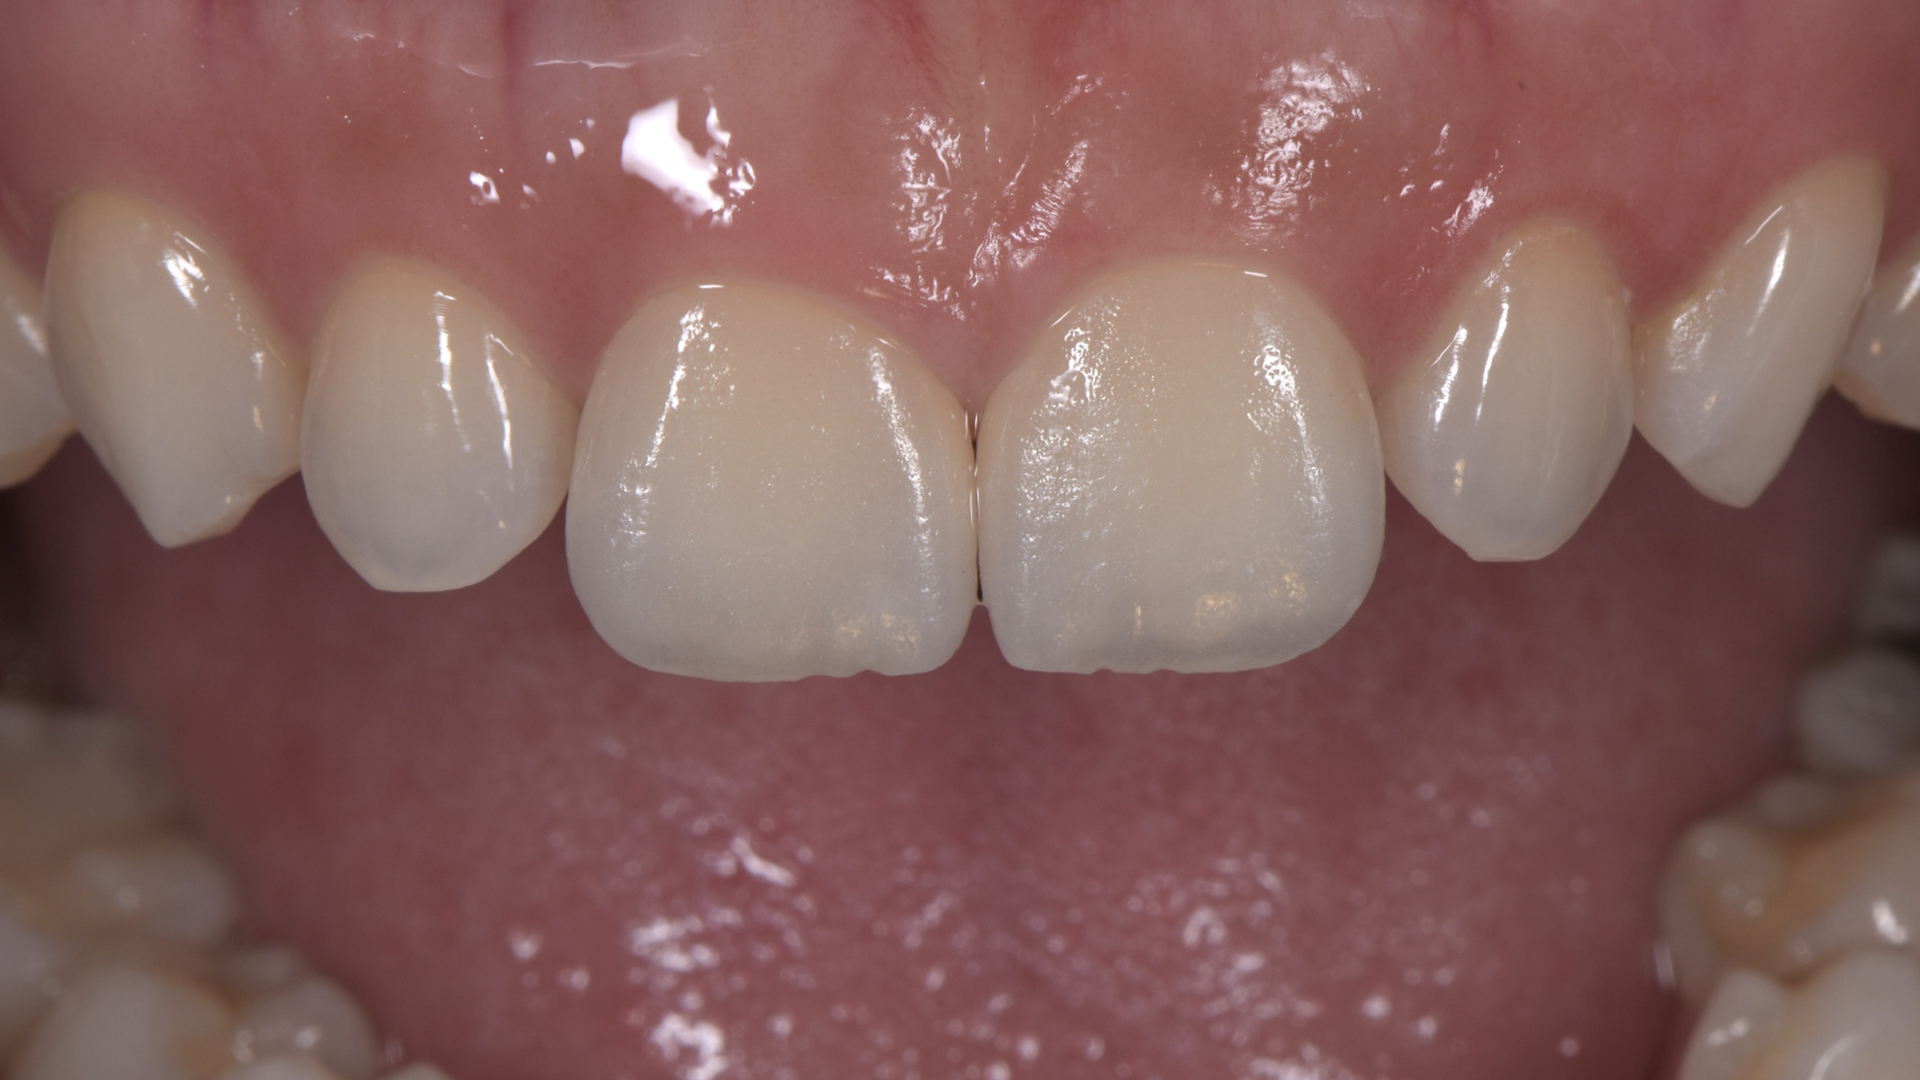

顯微貼片